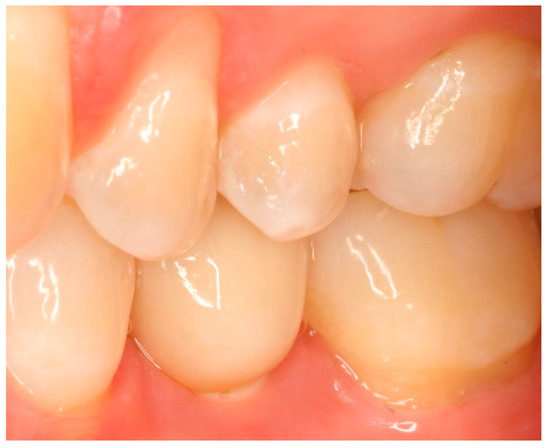

Situation after crown cementation. Lateral view.

Figure A14.

Clinical situation at the 1-year follow-up. Lateral view.

Figure A17.

Clinical situation at the 3-year follow-up. Lateral view.

Figure A20.

Clinical situation at the 5-year follow-up. Lateral view.

Figure A23.